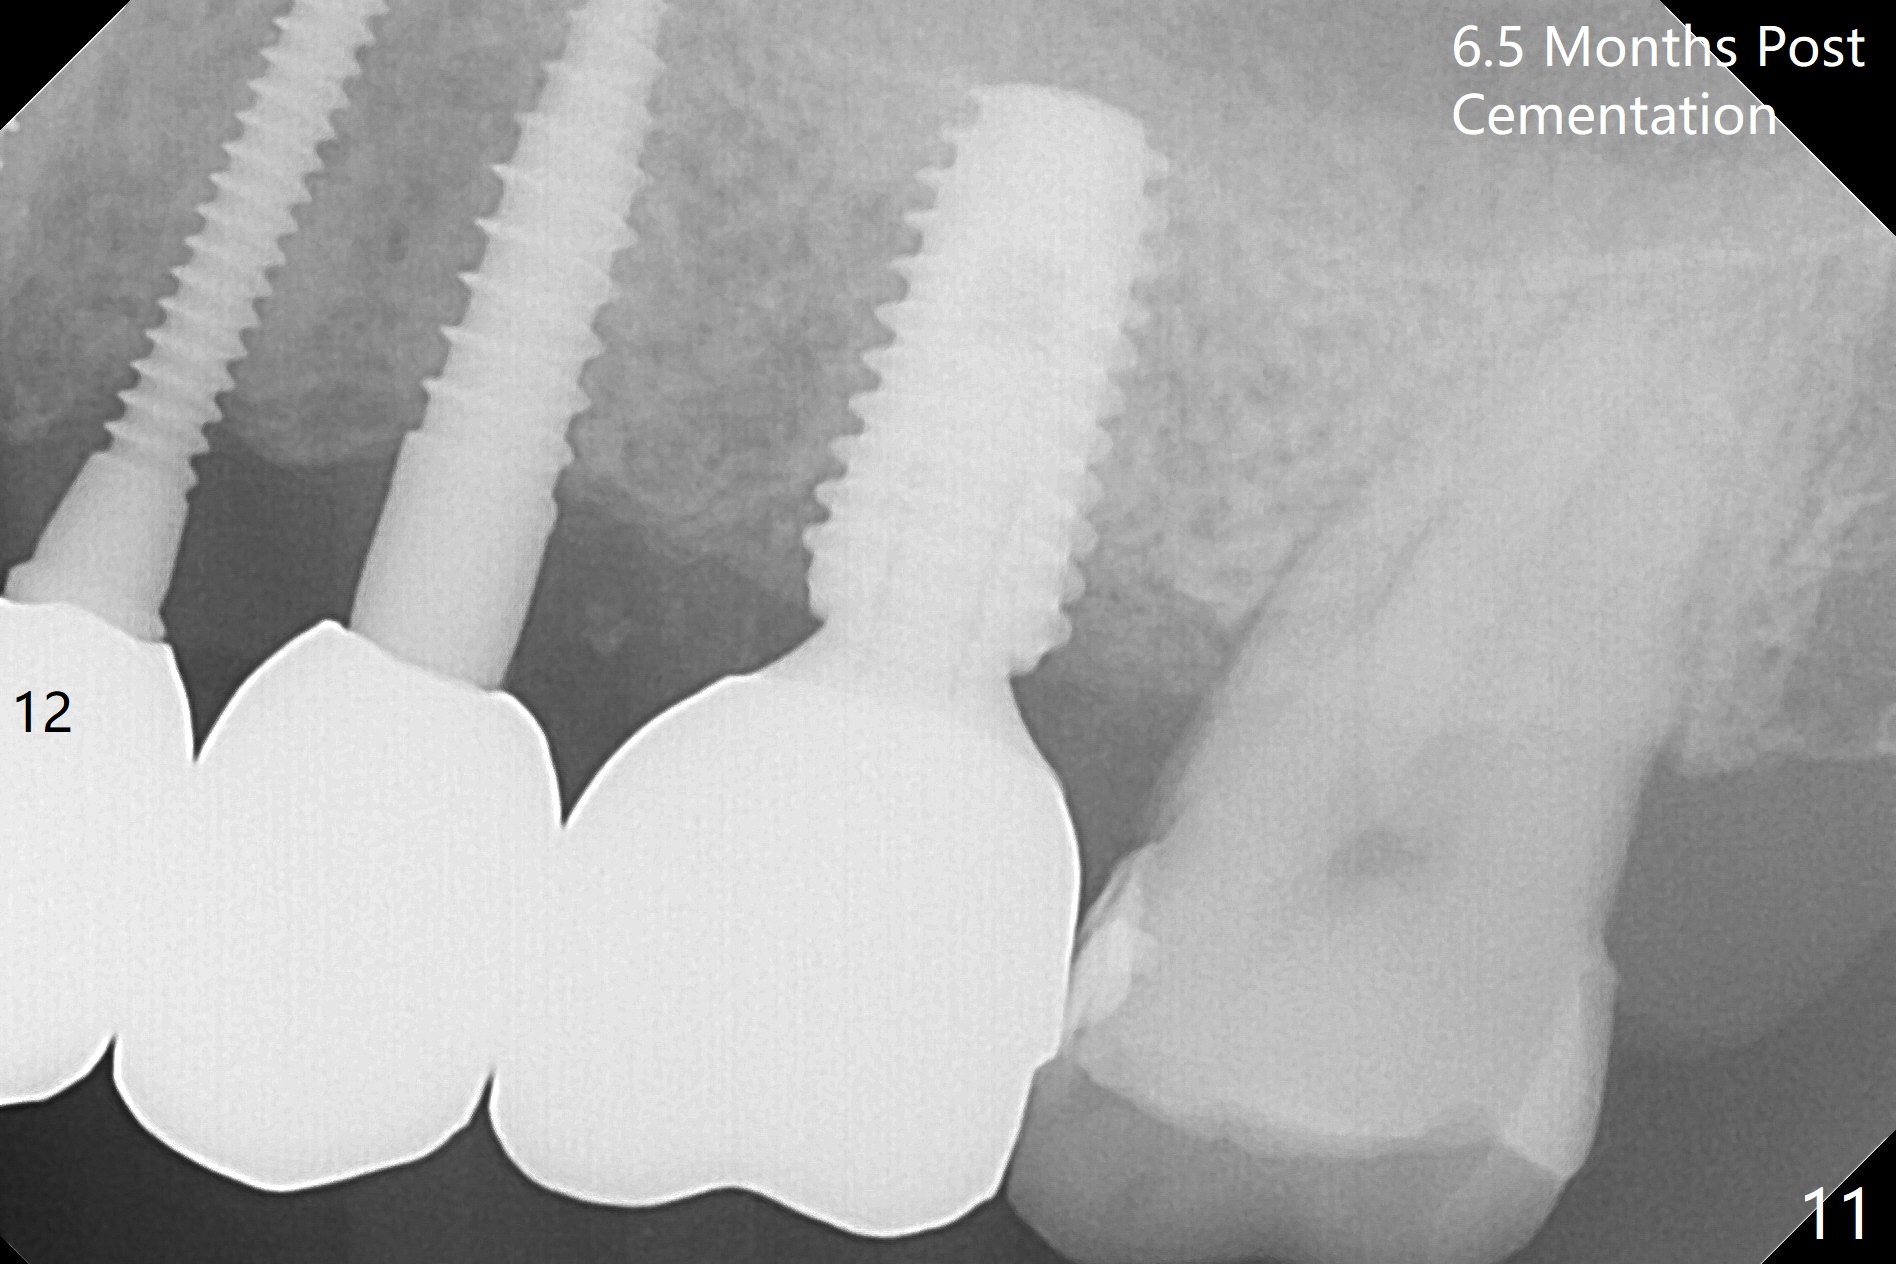

The edentulous ridge is narrow between the residual roots of #11 and 14 (Fig.1). Since the bone density is low in the edentulous area, DIO bone expanders are used (e.g., #1 (1/1.6 mm) Fig.2) after 1.2 mm initial drill. A 2x14(2) mm 1-piece implant is placed at #12 with 4 mm ridge width, while a 3x10 (2) mm dummy implant is partially placed after use of Bone Expander #2 (1.3/2.3 mm). The latter is replaced by a definitive one (3x12(2) mm), while the one at #12 is placed deeper (Fig.4). After extraction and placement of PRF and Vanilla Graft for sinus lift (Fig.4 black *), a 5x10 mm 2-piece implant is placed at #14, while a dummy implant is placed at #11 (Fig.4,5). As the osteotomy at #11 is 4.9 mm longer than the dummy (Fig.5), a definitive one is 3 mm longer (Fig.6). Osteogen plug is placed in the apical portion of each socket at #11 and 14, while Vanilla and Osteogen are packed in the coronal portion of the socket (Fig.4,6 *). Although primary stability of each implant is not high (30/40 Ncm), splinted provisional with occlusal clearance seems to be sufficient for implant osteointegration. There is no discomfort 9 days postop (Fig.7). Impression is taken 3 months postop, since he plans to return to home country for business (Fig.8). Single unit crowns are cemented 4 months postop (Fig.9,10). The abutment screw at #14 needs retightening 6 months post cementation. The access hole slightly buccal. Chewing pain at #12 is reduced after occlusal adjustment 6.5 months post cementation (Fig.11).